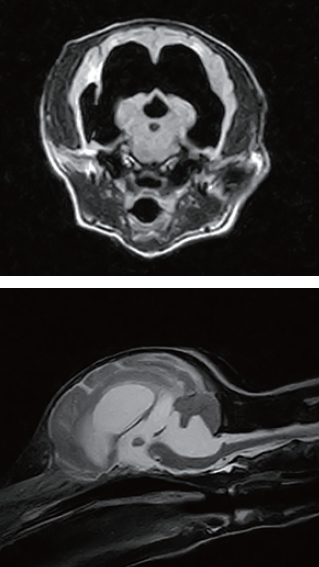

頭部MRI検査より、先天性水頭症、脳挫傷、頚髄挫傷と診断した。 先天性水頭症による進行性の神経症状が基礎にあり、脳挫傷、頚髄挫傷は階段から落下したことに起因する続発障害であると判断した。